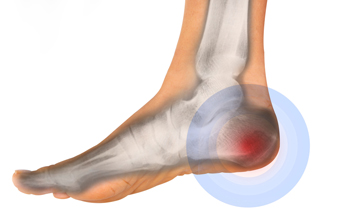

Heel bursitis occurs when the small fluid-filled sac, known as the retrocalcaneal bursa, becomes irritated and inflamed at the back of the heel where the Achilles tendon meets the heel bone. This irritation can develop from repetitive activities that increase pressure in that area, including running uphill, jumping, or standing on tiptoes. Wearing high heels frequently, ill-fitting shoes that rub against the heel, or flip-flops that provide little protection may also contribute to heel bursitis. Tight calf muscles or an existing bone spur can further aggravate the bursa. Symptoms include swelling, tenderness, and a painful lump at the back of the heel, which worsens when shoes press on the area or when engaging in activities that put stress on the Achilles tendon. A podiatrist can evaluate the heel and provide the most effective treatment. If you experience symptoms of bursitis in the heel, it is suggested that you schedule an appointment with a podiatrist for an exam and appropriate treatment.

Causes of Heel Pain

Heel pain is often associated with plantar fasciitis. The plantar fascia is a band of tissues that extends along the bottom of the foot. A rip or tear in this ligament can cause inflammation of the tissue.

Achilles tendonitis is another cause of heel pain. Inflammation of the Achilles tendon will cause pain from fractures and muscle tearing. Lack of flexibility is also another symptom.

Heel spurs are another cause of pain. When the tissues of the plantar fascia undergo a great deal of stress, it can lead to ligament separation from the heel bone, causing heel spurs.